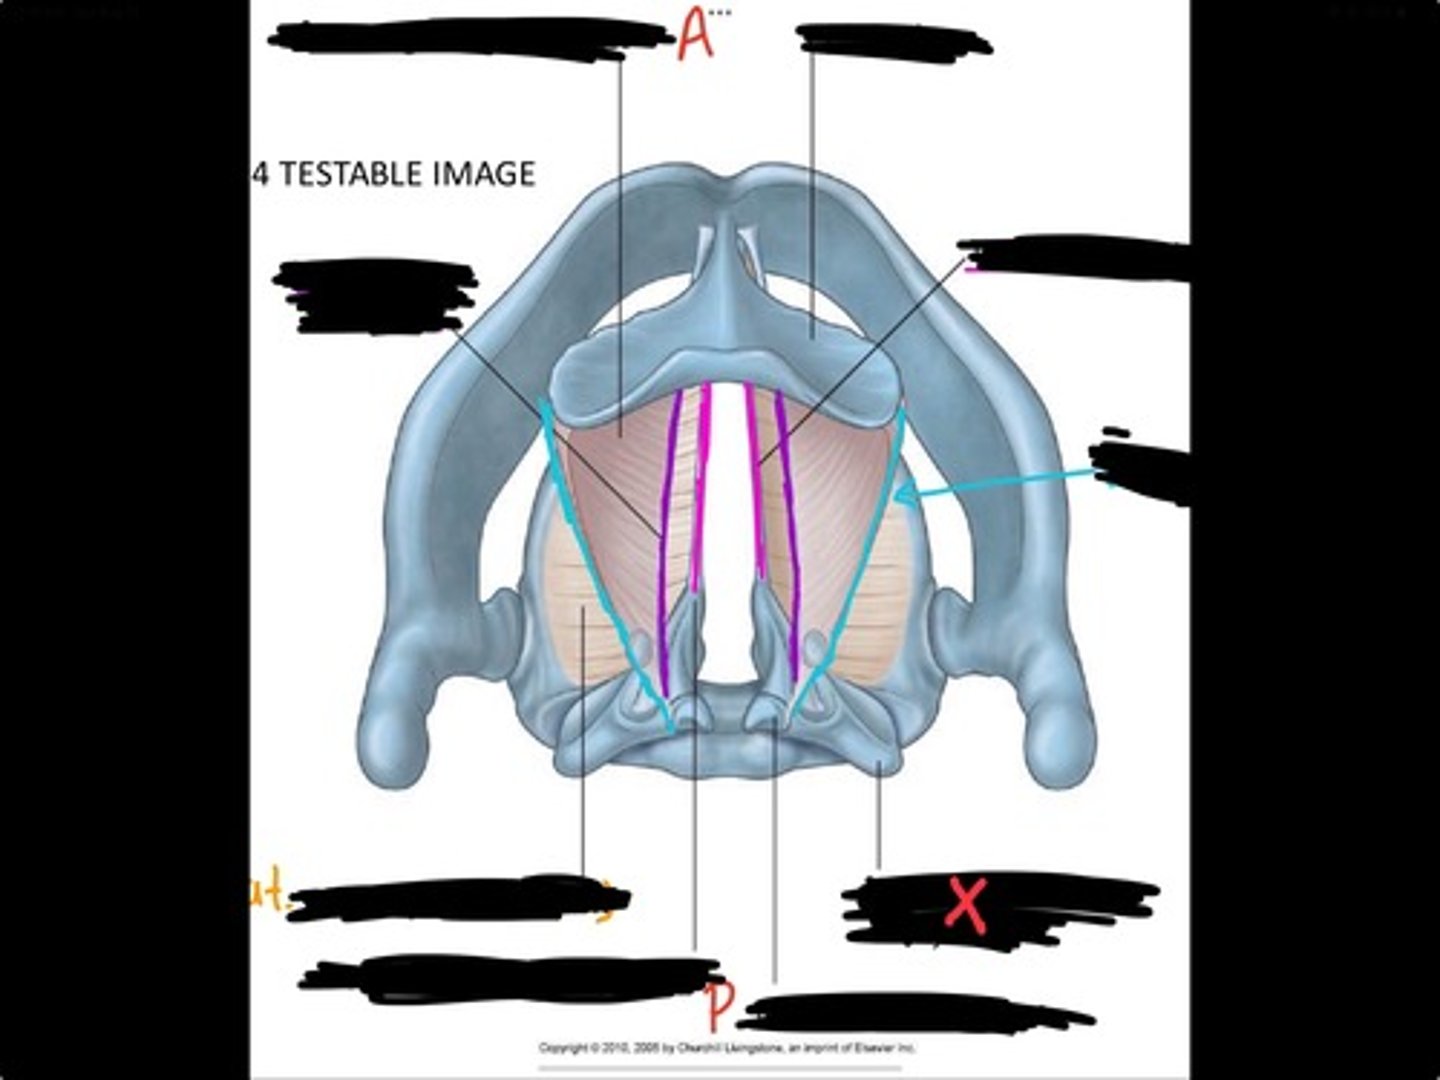

Vocal process of arytenoid

Conus elasticus

Vestibular ligament

Quadrangular membrane

Epiglottis

vocal ligament

Aryepiglottic ligament

Muscular process of arytenoid

Corniculate cartilage

Posterior crico arytenoid

oblique arytenoid

transverse artyenoid

Rima glottidis

Vocal ligament

Vocalis muscle

Lateral cricothyroid ligament

Lateral cricoartenoid